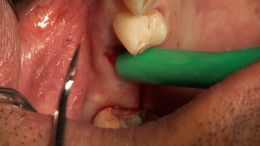

اصول مبانی GBR

+ اساتید گروه علمی بن تاژ پارس (زیرنظر پروفسور غلامی)

- جراحي توسط دکتر عميد از اساتید گروه علمی بن تاژ